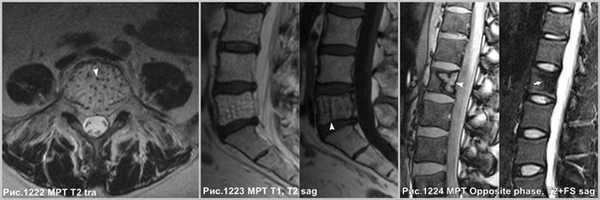

Гемангиомы позвонков представляют собой очаговые образования, без масс-эффекта, вызывающие рассасывание большинства вертикальных балок позвонка, однако сохраняющиеся балки склерозируются и утолщаются. В целом вертикальная резистентность позвонка снижается, что может осложняться патологическими переломами. Считается, что гемангиома, содержащая большое количество жира, с меньшей вероятностью, будет расти или станет клинически значимой [87].

Крупная гемангиома в теле L5 позвонка, распространяющаяся на всё его тело, приводящая к перестройке губчатого вещества кости, с разряжением губчатого вещества и наличием вертикальных утолщенных костных балок (головки стрелок на рис.1222,1223). Гемангиома в теле позвонка, имеющая жировую интенсивность МР-сигнала - ↑сигнал по Т1, с обозначением контура на последовательности в противофазе (головка стрелки на рис.1224), и имеющая выпадение МР-сигнала в режиме Т2 с жироподавлением (стрелка на рис.1224), что соответствует жировой ткани в гемангиоме.